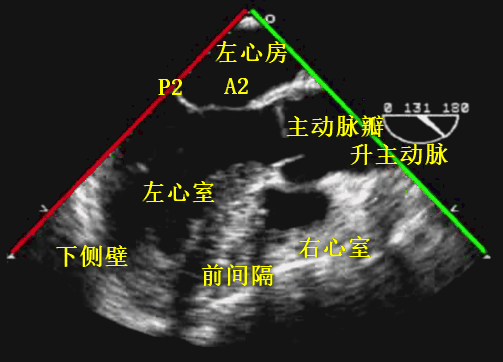

超声探头位置与前述两腔心切面时一致、位于左心房后部,旋转晶片角度至 130° 左右(图 14)。可在长轴方向显示主动脉瓣和左室流出道,调整超声探头深度使得整个左心室在图像中显示。左心室前间膈和下侧壁、二尖瓣 A2 及 P2 均能清晰显示(图 15)。

图 14:TEE 切面示意图(LAX view)

A:后前位;B:前后位剖开结构;C:旋转图像转换

该切面用于诊断二尖瓣、主动脉瓣、主动脉根部和室间隔病变,也可用于评估左室功能。此切面也是二尖瓣缘对缘修复术(TEER)中的重要参考依据。